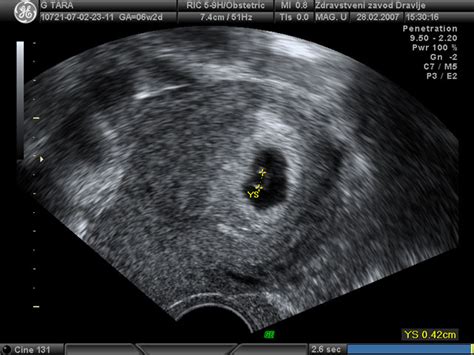

V 10. tednu nosečnosti ultrazvok že kaže majceno, a vse bolj oblikovano človeško bitje. Dolžina ploda meri od 3 do 4 centimetrov, kar je primerljivo s plodom kumkvata ali fige, njegova teža pa je okoli 4-5 gramov. Glava je še vedno nesorazmerno velika glede na preostanek telesa, kar je značilno za zgodnje faze razvoja, a se že jasno vidijo obrisi obraza. V razvijajoči se čeljusti se oblikujejo drobni zametki zob.

Če še niste obiskali zdravnika, je zdaj pravi čas, da se dogovorite za termin za predporodno varstvo, vključno s prvim ultrazvočnim pregledom. V 10. tednu nosečnosti se lahko odločite za genetske presejalne teste. Merjenje nuhalne svetline se opravi med 10. in 14. tednom, na voljo pa je tudi Nifty test, ki ga je možno opraviti od 10. tedna dalje. Najbolj zanesljiva metoda za ugotavljanje nepravilnosti je amniocenteza, ki pa se običajno izvaja le v primeru genetskih nepravilnosti v družini ali slabih rezultatov drugih testov. Ta se izvaja med 15. in 20. tednom.